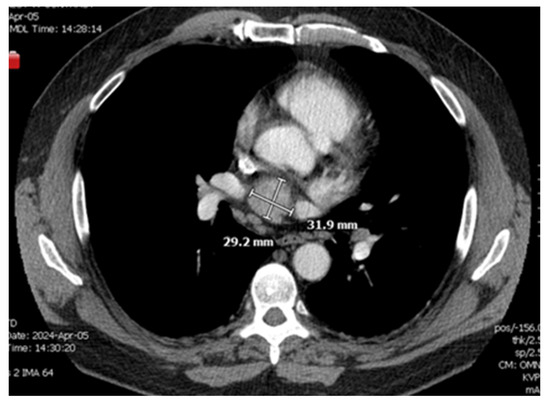

A CT chest scan, now with contrast, was completed on 4/5 and demonstrated a solid mildly enhancing 3.2 cm mass located just superior to the left atrium and just inferior to the right pulmonary artery consistent with findings from the nuclear medicine scan (Figure 1 and Figure 2). There remained a concern for ectopic parathyroid tissue but also a malignant tumor, hence a recommendation was made for tissue sampling. Parathyroid exploration was deferred given that orthotopic parathyroid pathology did not appear to be the source. Thoracic surgery was consulted for possible surgical removal of the gland; however, there was concern about safe accessibility given the location of the gland.

Figure 2. Re-demonstration of mediastinal mass in Axial CT scan.